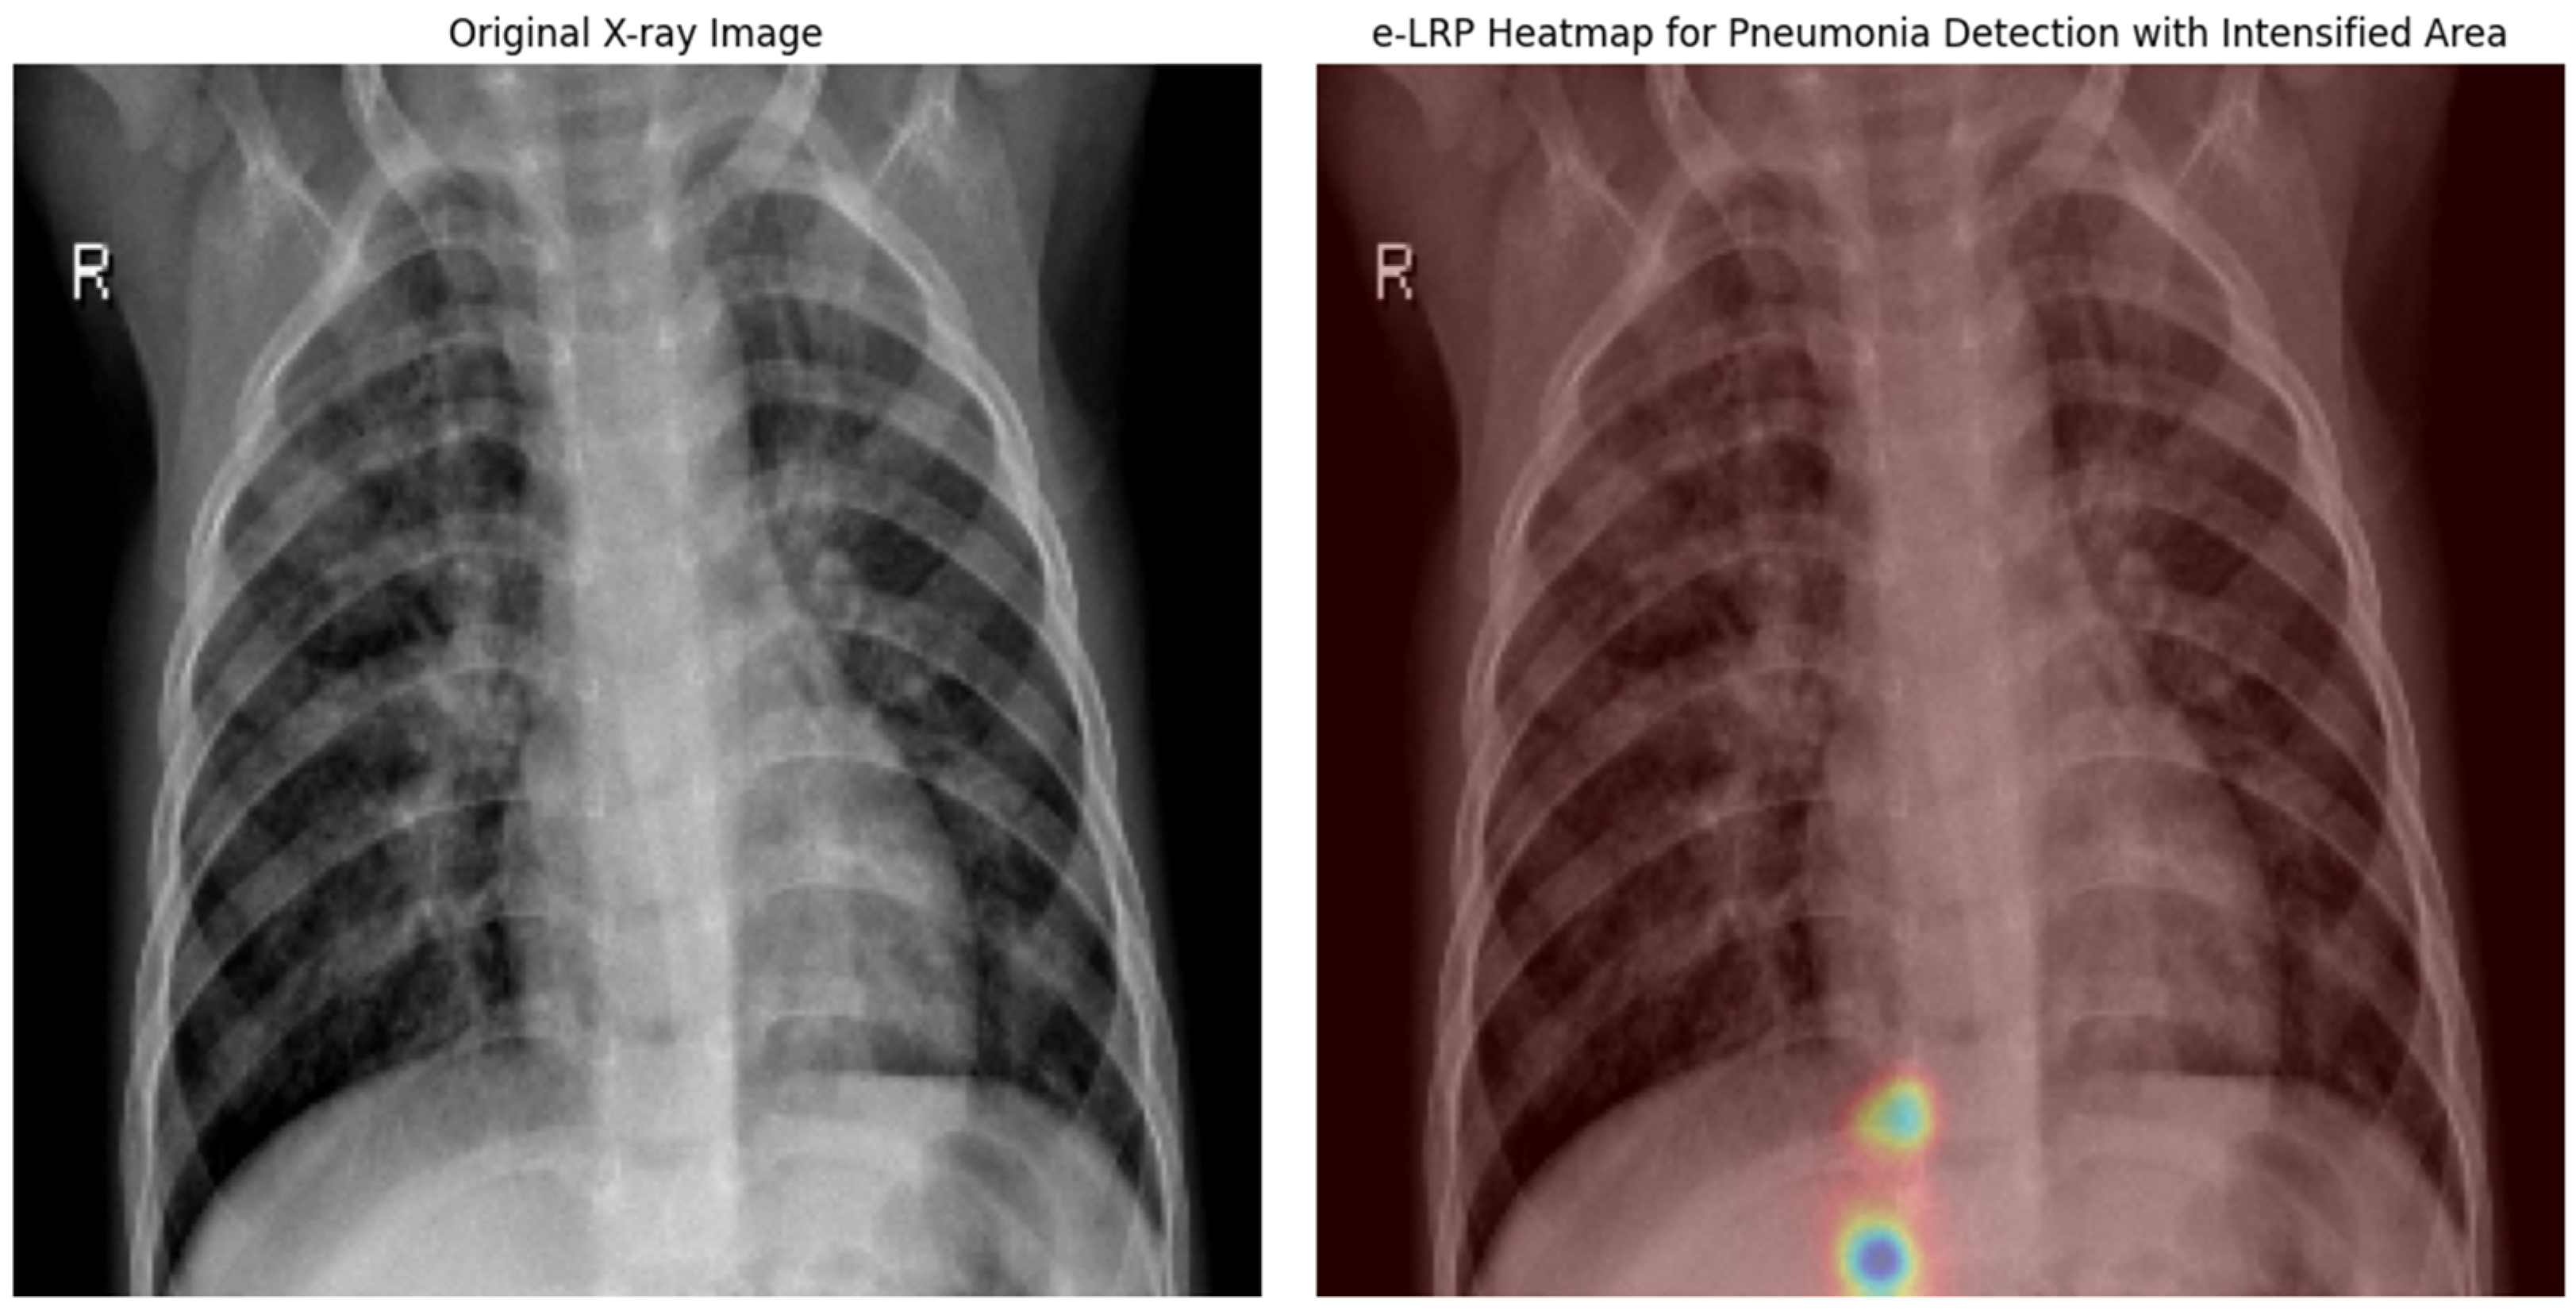

- Layer-wise Relevance Propagation (LRP): This method utilizes the epsilon variant (ε = 0.001), ensuring numerical stability and a clear relevance distribution across layers. Adjusting the epsilon refines the pixel-level relevance, yielding high interpretability without performance trade-offs, making LRP especially suitable for clinical settings.

- LRP was refined through adjustments to its epsilon parameter, achieving the highest MRS possible with no significant trade-offs in accuracy, which made it the best-optimized technique for interpretability without performance loss.

4.3. Layer-Wise Relevance Propagation Implementation Results